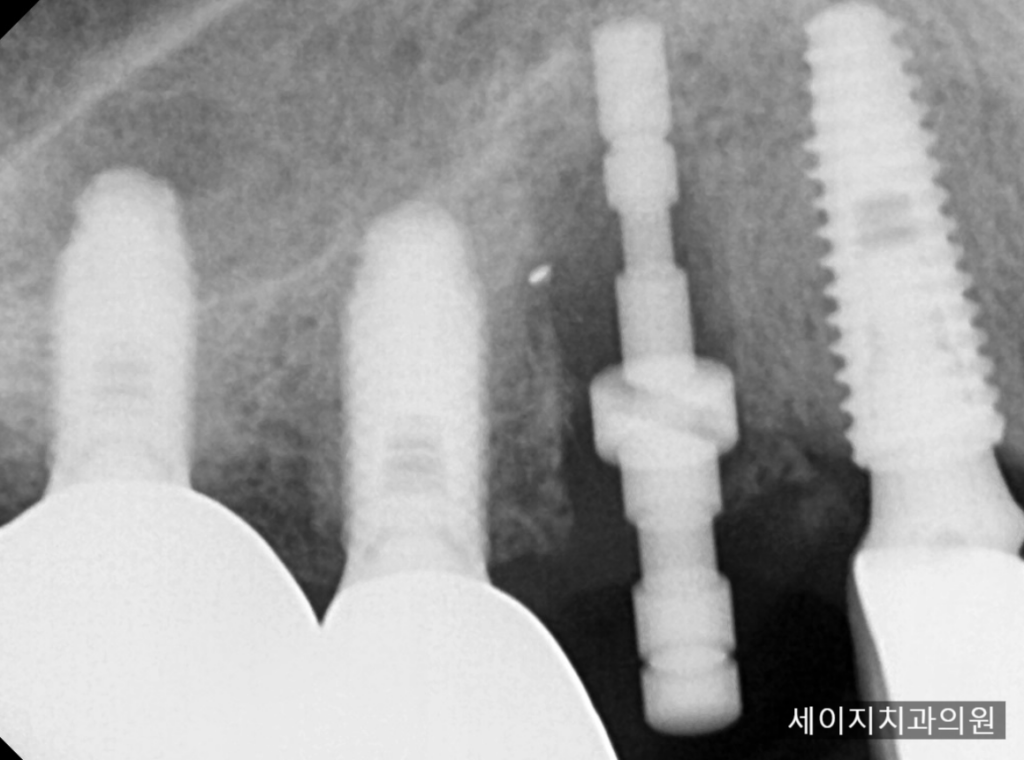

24. 12. 09

임플란트 주변부의 골삭제는 상대적으로 골조직이 많았던 임플란트의 앞부분을 통해 이루어 졌고

이후 공간을 부여한 뒤, 임플란트를 발치하듯이 제거하였습니다.